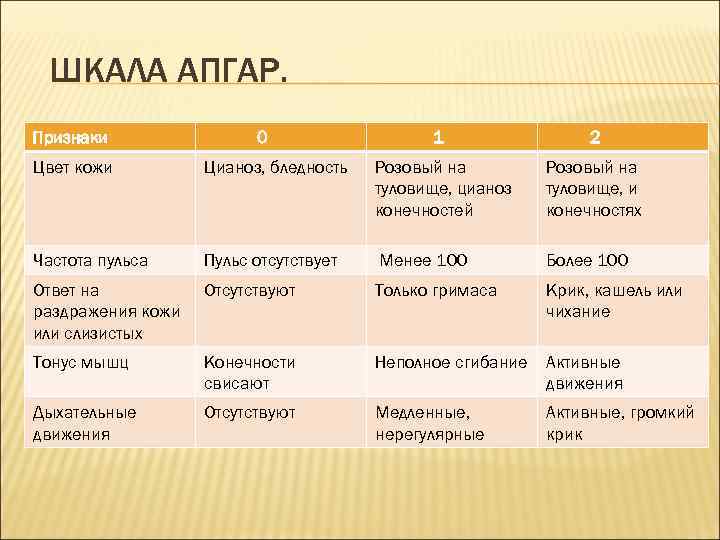

Сводка этих признаков с их бальной оценкой, предложенная Вирджинией Апгар в 1953 г. , используется врачами всего мира для характеристики состояния новорожденного ребенка и принятия решений о необходимости, степени экстренности и объеме медицинской помощи. Оценку производят на 1 -й минуте после рождения и повторно на 5 -й минуте

ШКАЛА АПГАР. Признаки 0 1 2 Цвет кожи Цианоз, бледность Розовый на туловище, цианоз конечностей Розовый на туловище, и конечностях Частота пульса Пульс отсутствует Менее 100 Более 100 Ответ на раздражения кожи или слизистых Отсутствуют Только гримаса Крик, кашель или чихание Тонус мышц Конечности свисают Неполное сгибание Активные движения Дыхательные движения Отсутствуют Медленные, нерегулярные Активные, громкий крик